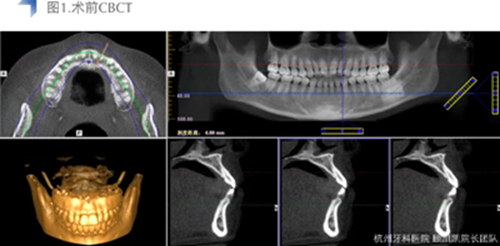

接診后口內(nèi)檢查12近中鄰面較大面積齲齒,探不適,叩無不適,冷熱測試同時對照牙及臨牙,BOP+,捫診(-),未有異常松動度。術(shù)前CBCT檢查如下圖,未見明顯根尖周透射影。